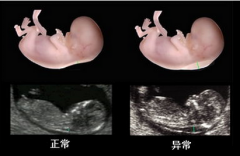

产前检查孕期系统彩超贵阳哪家医 产前检查贵阳市做系统彩超多少钱 产前检查系统彩超与三维彩超的区 产前检查做胎儿心脏彩超需要预约

【导读】贵阳市做四维彩超费用多少钱?随着现代科技的发展,推动医疗设备的不断更新... [详情]

四维彩超四维彩超需要憋尿么不需 四维彩超四维彩超需要空腹吗不需 四维彩超四维彩超有必要做么 四维彩超贵阳市做四维彩超多少钱